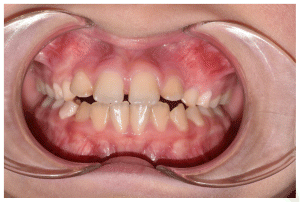

Case 2

The patient was a growing female child who presented during early mixed dentition with an anterior crossbite associated with a deep overbite and a marked sagittal discrepancy (Figures 12–19). The initial clinical examination revealed a negative overjet, complete anterior deep bite, and a functional Class III occlusal pattern. Extraoral assessment showed a flattened facial profile, while cephalometric analysis confirmed a skeletal imbalance characterized by increased SNA and SNB values, an ANB of 0°, negative Withs appraisal, and significant dentoalveolar compensations, including proclination of both upper and lower incisors (Table 3). The vertical pattern was predominantly hypodivergent, suggesting a high risk of unfavorable mandibular growth progression if left untreated. Given the patient’s young age and growth potential, an early interceptive treatment was planned to use the AMCOP® TC appliance, with the aim of correcting the anterior crossbite, improving neuromuscular balance, and guiding sagittal and vertical development during growth. The appliance was worn nightly and for additional daytime hours, according to patient compliance.